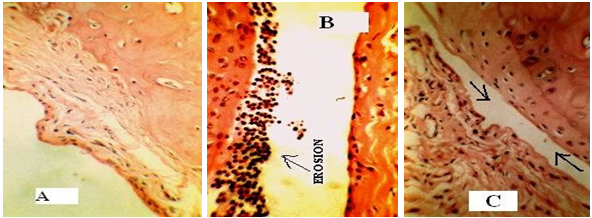

Section of the synovial joint of a normal control rat shows intact articular hyaline cartilage (fig. 3(A), subchondrial bone layer and adjacent synovial layer. The synovial layer shows synovial lining cells within a normal range. The synovial subepithelium shows fibro-collagenous stroma with vascular spaces (fig. 3 (A)). Section of the synovial joint of CFA treated rat shows partially distorted articular hyaline cartilage with intact subchondrial bone layer and partially effaced synovial layer. The distorted articular cartilage, i.e., bone erosion is replaced by mixed inflammatory cells comprising predominantly neutrophil and some lymphocytes. The synovial sub epithelium shows fibro collagenous stroma with vascular spaces (fig. 3 (B)). Section of the synovial joint of Dr. Ortho treated shows intact articular hyaline cartilage (fig. 3 (C)), subchondrial bone layer and adjacent synovial layer. The synovial layer shows synovial lining cells within normal range. The synovial sub epithelium shows fibrocollagenous stroma with vascular spaces (fig. 3 (C)).

Fig. 3: (A)-TS of the knee joint of normal control rat, showing no mononuclear infiltration and pannus formation [H&E, 100×]. (B)-TS of the knee joint of with bone erosion [H&E, 400×]. (C)-TS of knee joint of with reduced bone erosion [H&E, 100×]

Pannus formation is one of the major events which lead to cartilage destruction and bone erosion in rheumatoid arthritis. The pannus formed due to CFA was reduced by Dr. Ortho. It is supported by histological studies of knee joints [18]. fig. 3 (A) is TS of knee joint of control rat. Severe neutrophil infiltration, pannus formation and bone erosion are seen in the knee joint of arthritic control rat as shown in fig. 3 (B). On treatment with Dr. Ortho, there is a reduction in the neutrophil infiltration, pannus formation and bone as shown in fig. 3 (C), respectively. Loss of body weight occurs in arthritis due to deficient absorption of nutrients through the intestine and distress caused by the severity of arthritis [19]. Dr. Ortho decreased the elevated level of WBC, thus leading to a reduction in mononuclear infiltration and hence reduced pannus formation.